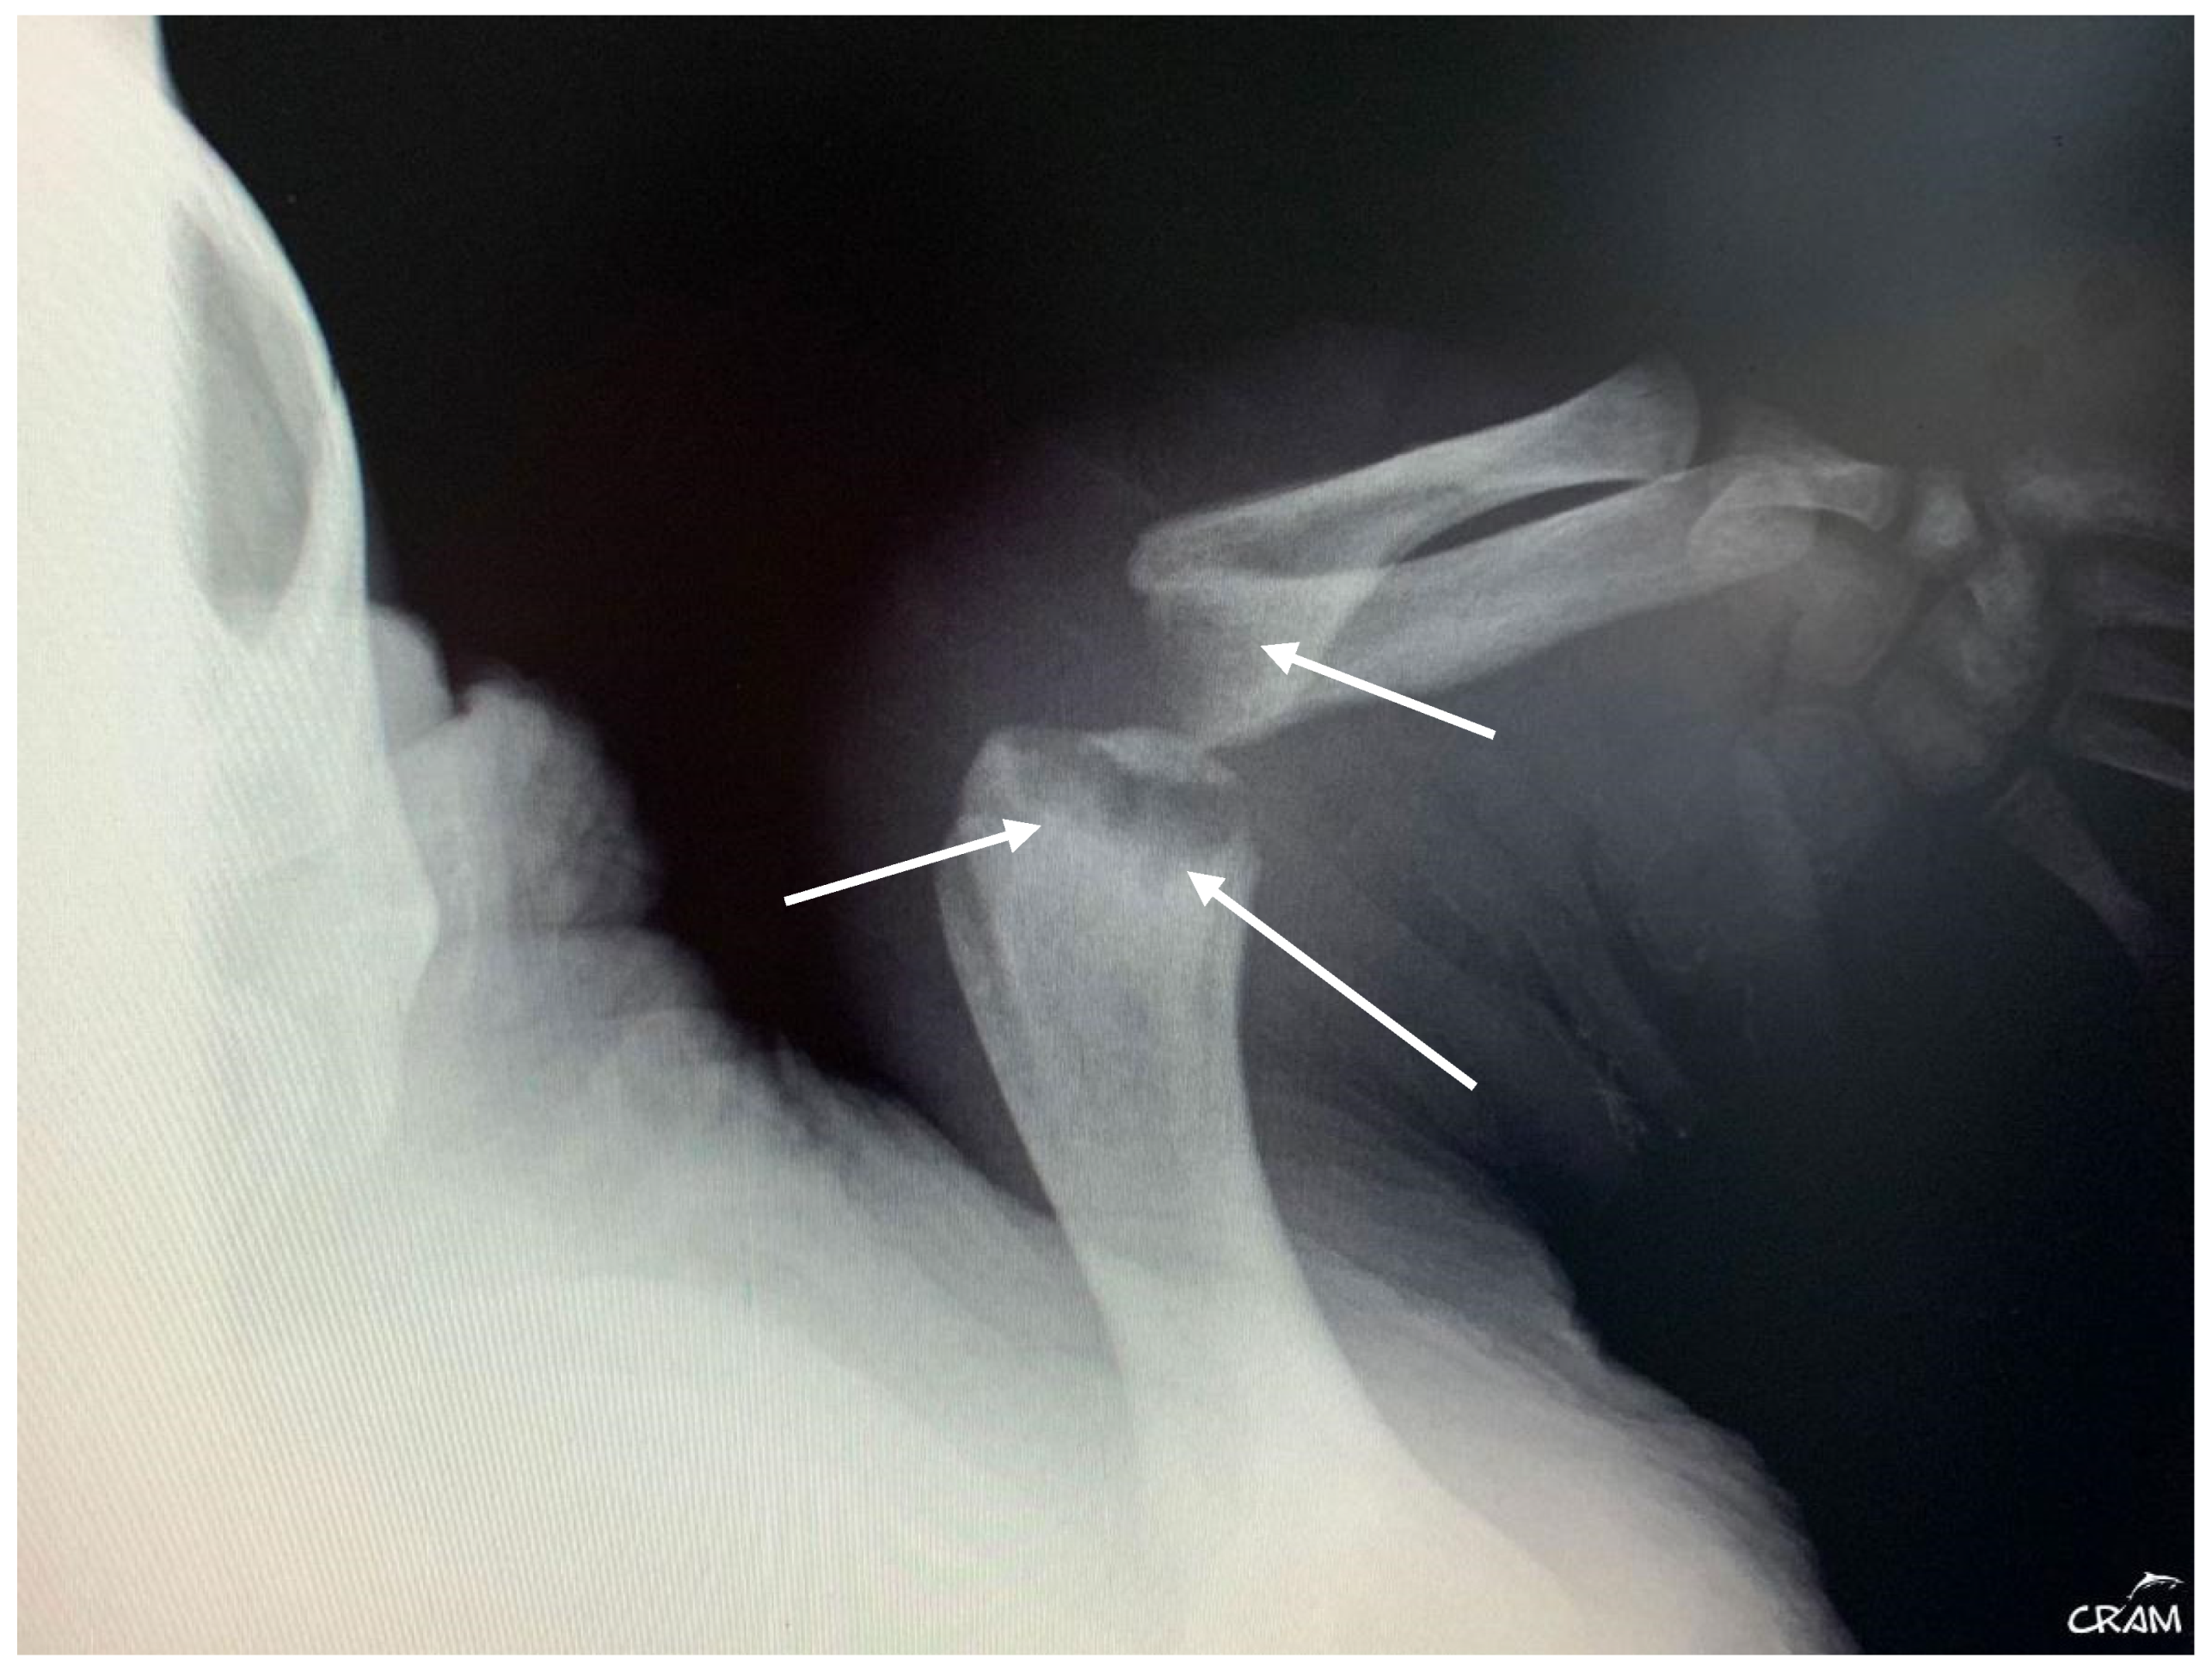

Hard edema with increased periarticular soft tissue and pain was noticed at palpation during clinical evaluation in veterinary medicine [21]. At the beginning of signs, radiographic lesions were polyostotic and poorly defined (Figure 5 and Figure 6).

Figure 5.

Dorsoventral radiograph of the right front flipper at day 45 of rehabilitation. Well-defined bone lesions (arrows) are noted. Lesions are lytic with relevant osteopenia and no bone remodeling. The lytic process is seen communicating with the joint space in the elbow joint.

Early-stage lesions at day 45 of rehabilitation were characterized by a purely osteolytic process restricted to the distal end of the humerus and femur and the proximal end of the radius, ulna, and tibia, including demineralization of the surrounding bones. Osteolytic lesions were restricted to the epiphysis and metaphysis of long bones, and no lesions were detected in the diaphysis.

Dorsoventral radiographic of the right flipper after five months of rehabilitation. Well-defined sclerosis surrounding rounded lesion borders is noted (arrows).

X-ray is the initial imaging of choice for diagnosis and evaluation of bone lesions. Although radiography showed decalcification and cystic lesions on some bones, it demonstrated a lower sensitivity compared to the CT. One of the hypotheses is that the lesions observed in March 2023 were caused by the decompression sickness event that occurred four years earlier, representing a case of DON. DON is rare but remains extremely important to be recognized as a potential complication of DCS [5,6,11].